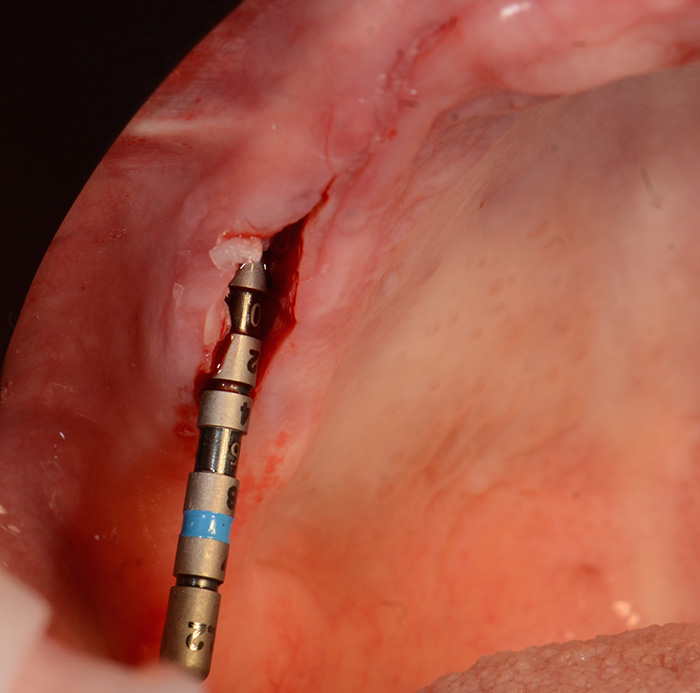

Fig. 6 : Placement d’un implant droit en zone de 12, le BLX par son coté agressif permet une stabilité primaire dans cette zone présentant un défaut osseux, mais sans entraîner de compression trop importante, ce qui permettra de garder intact le « pont » osseux au niveau créstal : bien meilleur pour le devenir du comblement osseux fait avec du Bio os° L.